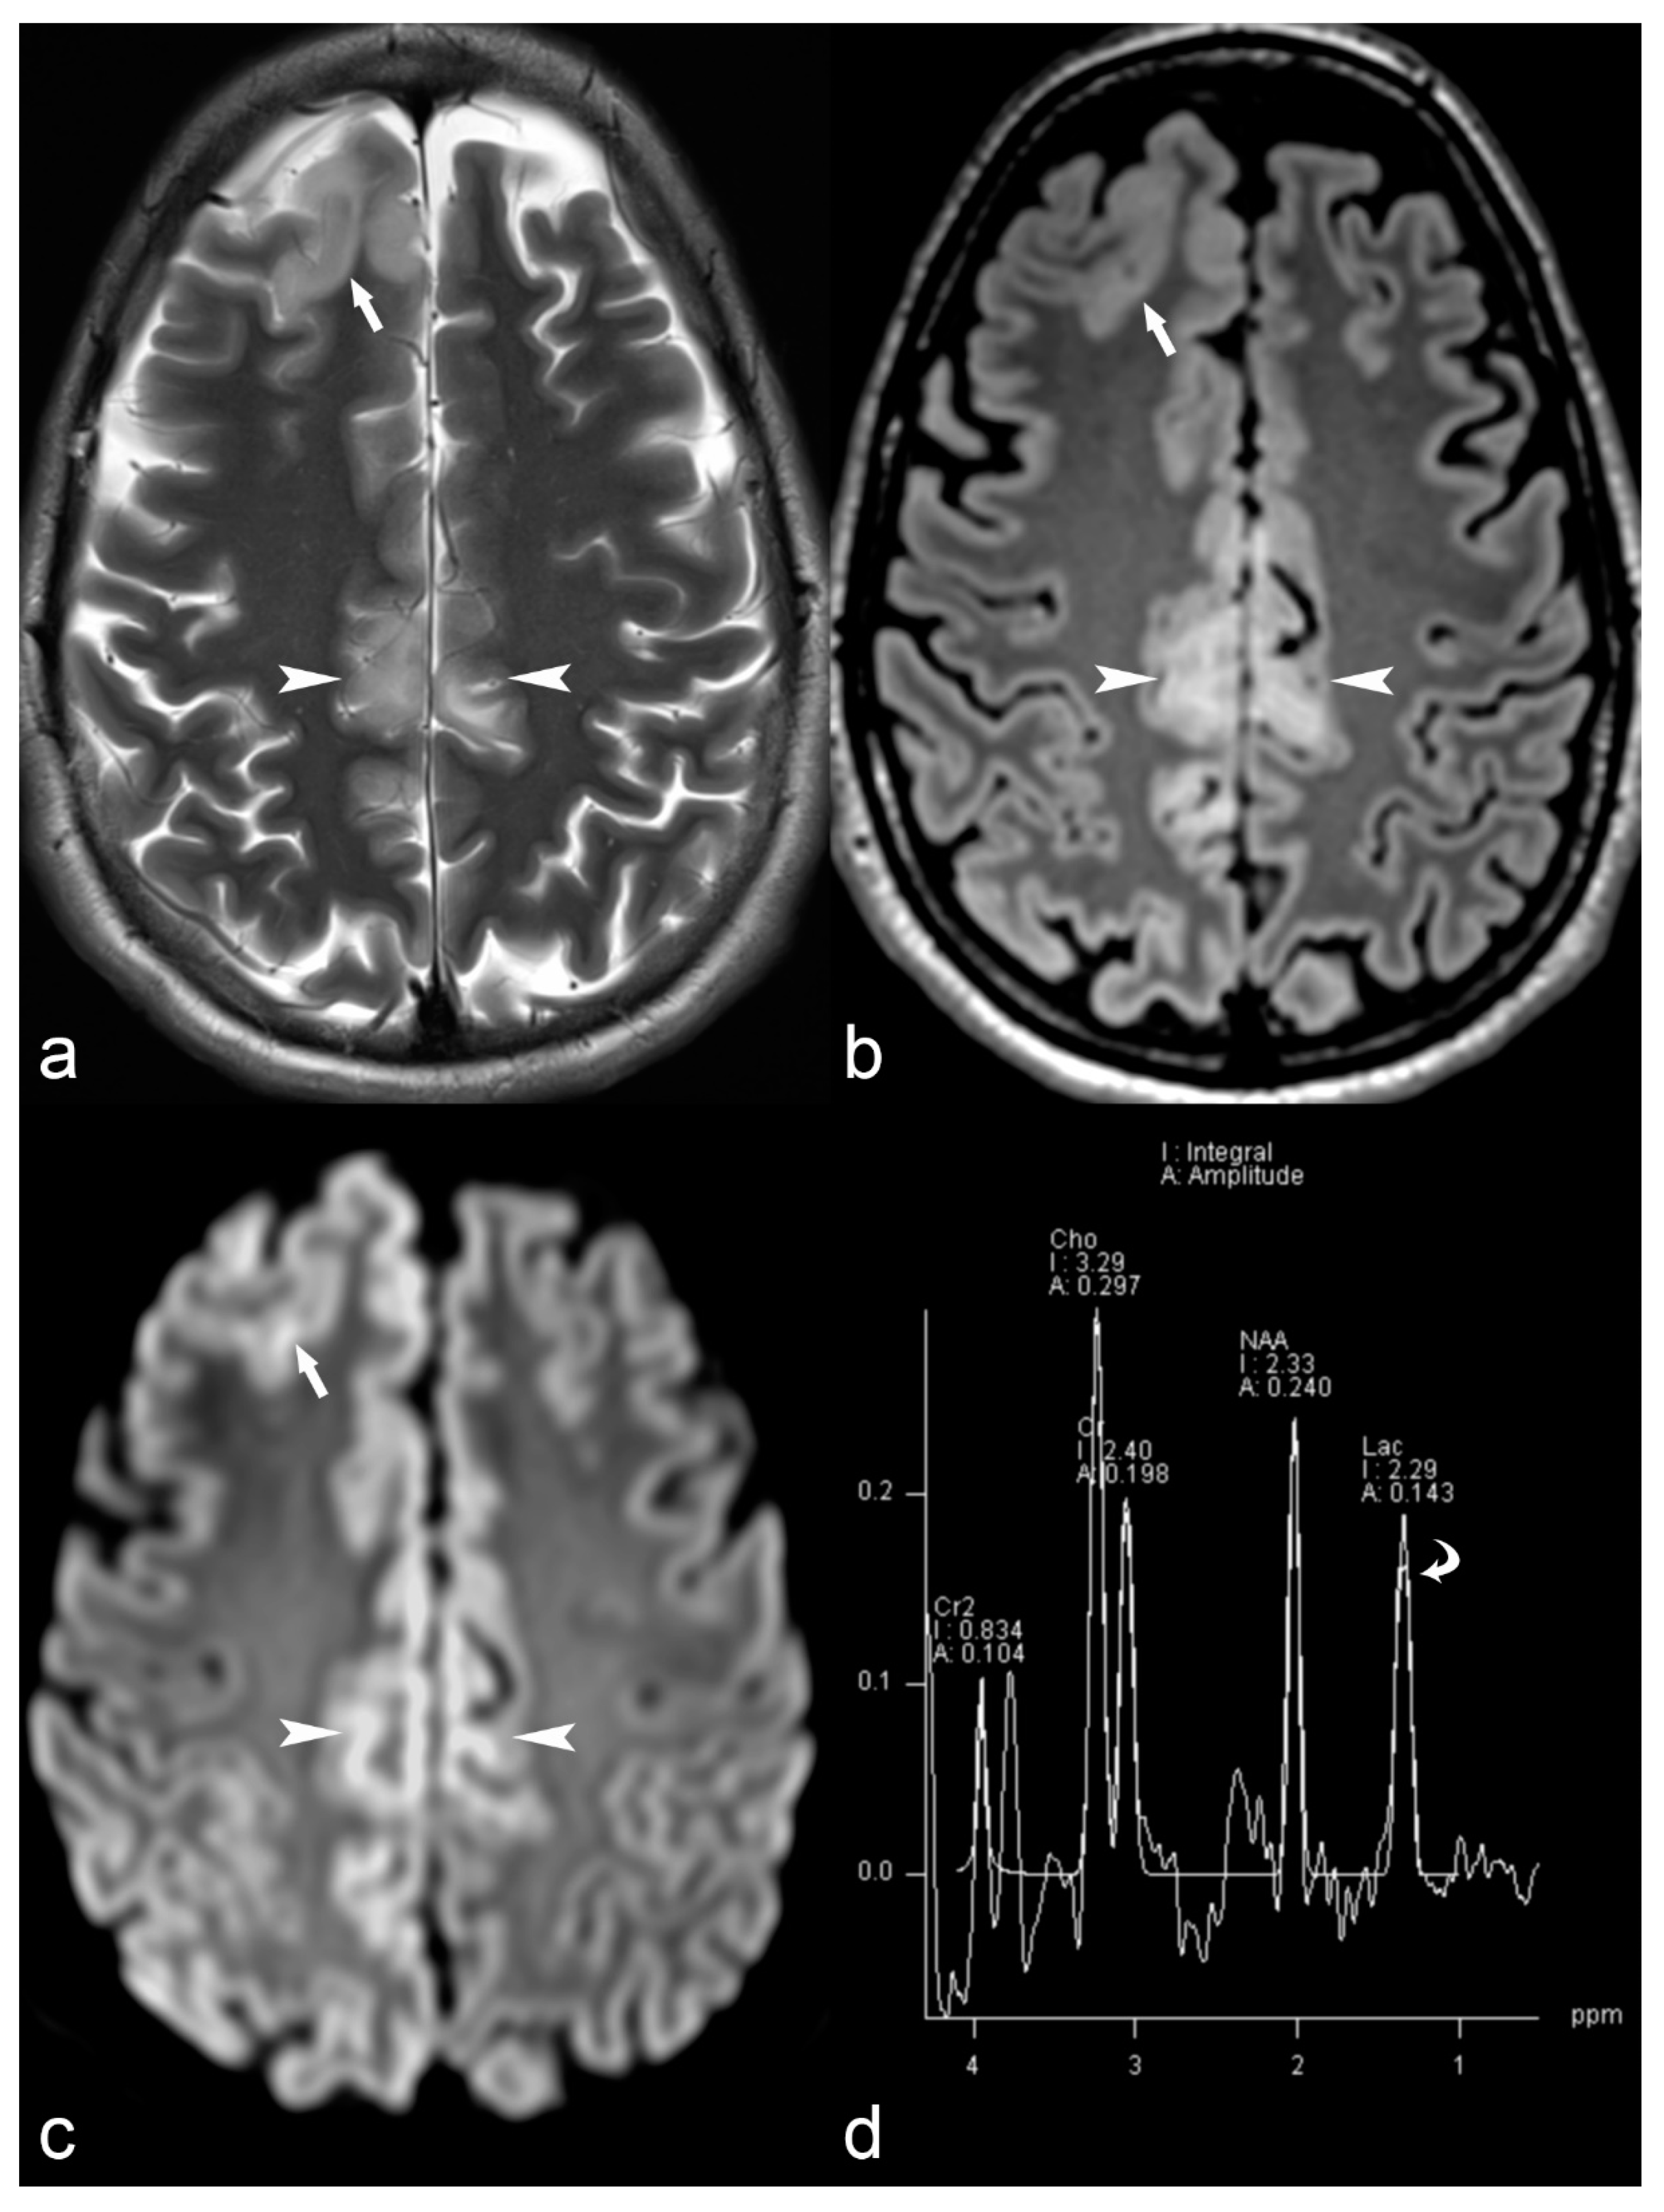

Magnetic resonance spectroscopy is an MRI technique that provides biochemical information on selective areas of the brain and can play an adjunctive role in the presurgical evaluation of certain patients with drug-resistant epilepsy. Different techniques including monovoxel or multivoxel studies have been used for the characterization of brain tumors, as well as for other pathologies, including leucodystrophies, metabolic disorders (Figure 1) or HS. MRS can also be useful in identifying the side of the epileptogenic focus in cases of temporal lobe epilepsy, demonstrating decreased N-acetyl aspartate (NAA) to creatine (Cr) ratio or NAA to choline (Cho) ratio in the pathologic site [56,57], frequently before morphological changes become apparent in conventional imaging.

Figure 1.

33-year-old female with MERRF (myoclonic epilepsy with ragged red fibers) and myoclonic epilepsy. Axial T2 (a), Fluid-attenuated inversion recovery (FLAIR) (b) and Diffusion weighted imaging (DWI) (c) trace images (b = 1000) show cortical thickening in the right frontal (arrow) and bilateral pericingulate region (arrowhead) with subcortical white matter hyperintensity and restricted diffusion (ADC images not shown). Magnetic Resonance (MR) spectrum (d) at short TE (35 ms) at the level of right pericingulate lesion (region of interest of 1 cm diameter) shows lactate peak at 1.33 ppm (curved arrow) consistent with mitochondrial encephalopathy.